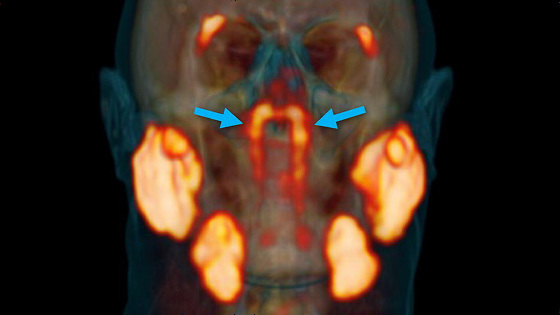

生物学家在对癌细胞的研究过程中 , 无意中发现了在人的鼻子到咽喉的深处有一对以前从未发现的器官 , 大小只有3.9公分 , 这个器官是唾液腺 。

上图可以看出 , 新的器官正位于上图中箭头标注的发光的地方 , 其他发光的地方就是我们以前认为的唾液腺所在的位置 。